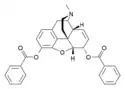

- Esters of morphine opiates: slightly chemically altered but more natural than the semi-synthetics, as most are morphine prodrugs, diacetylmorphine (morphine diacetate; heroin), nicomorphine (morphine dinicotinate), dipropanoylmorphine (morphine dipropionate), desomorphine, acetylpropionylmorphine, dibenzoylmorphine, diacetyldihydromorphine;[261][262]